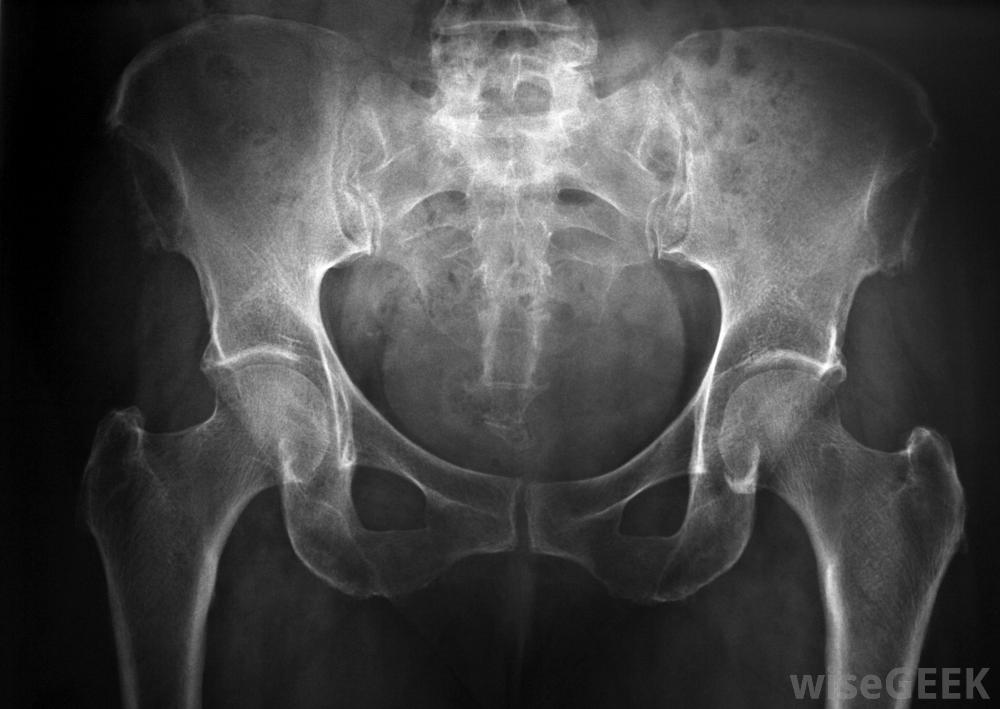

檢查結腸的異常和息肉通常需要一種特殊的診斷方法,即鋇灌腸或低G.I.(胃腸道)檢查。由于標準的x射線圖像不能提供清晰的結腸等軟組織的圖像,必須使用對比劑來提供更清晰的圖像在鋇灌腸中,這種對比劑是一種叫做硫酸鋇的金屬粉末。標準的x射線不能像結腸一樣捕捉到軟組織的良好圖像,因此必須使用對比劑在鋇灌腸開始之前,病人通常需要保持一個干凈的液體飲食,以清除結腸中殘留的糞便。可以使用標準灌腸來確保結腸盡可能的干凈。如果不清除糞便,糞便物質會擋住結腸某些部分的視野。一旦病人做好準備,他或她穿著醫院的長袍,被帶到一個檢查室。通過直腸進行鋇灌腸鋇灌腸的過程是從將硫酸鋇懸浮液通過直腸注入病人的結腸開始的。這是一種眾所周知的不舒服的體驗,在使用硫酸鋇時,許多病人會感到飽脹感或想排便一個小氣球可以防止造影劑從直腸中漏出。一旦硫酸鋇被充分分配,放射科醫生可能會要求病人采取幾種不同的體位來覆蓋結腸的每一個部分,甚至可以對病人的骨盆或腹部施加一些直接的壓力,以確保最大限度的覆蓋注射和調整硫酸鋇后,放射科醫生從不同角度拍攝了許多x射線圖像。由于硫酸鋇在標準x光片上呈白色,所以任何暗區都要仔細檢查是否有異常跡象。如果需要更多的清晰度,可以在最初的鋇灌腸后注射空氣進入結腸。病人可以在私人浴室里排出硫酸鋇,但通常有足夠的殘留物來為第二次檢查提供對比。并非所有的鋇灌腸程序都需要使用空氣來給結腸充氣,但人們相信改進的對比度值得額外的時間和精力小息肉可能很難通過標準的鋇灌腸來發現。一般鼓勵鋇灌腸檢查的標準年齡是50歲,盡管有結腸直腸疾病家族史的人可能會選擇早一點做一次。大多數人都能承受在鋇灌腸檢查之間等待5-10年,但是那些表現出其他結直腸癌癥狀或首次檢查結果有疑問的患者可能需要更頻繁地接受這種手術,鋇灌腸被認為是完全結腸鏡檢查的一種微創的替代方法,可能需要在麻醉下進行鋇灌腸可以提供許多與結腸鏡檢查相同的答案,而不會增加不適和恢復時間。僅通過標準鋇灌腸很難發現較小的息肉。